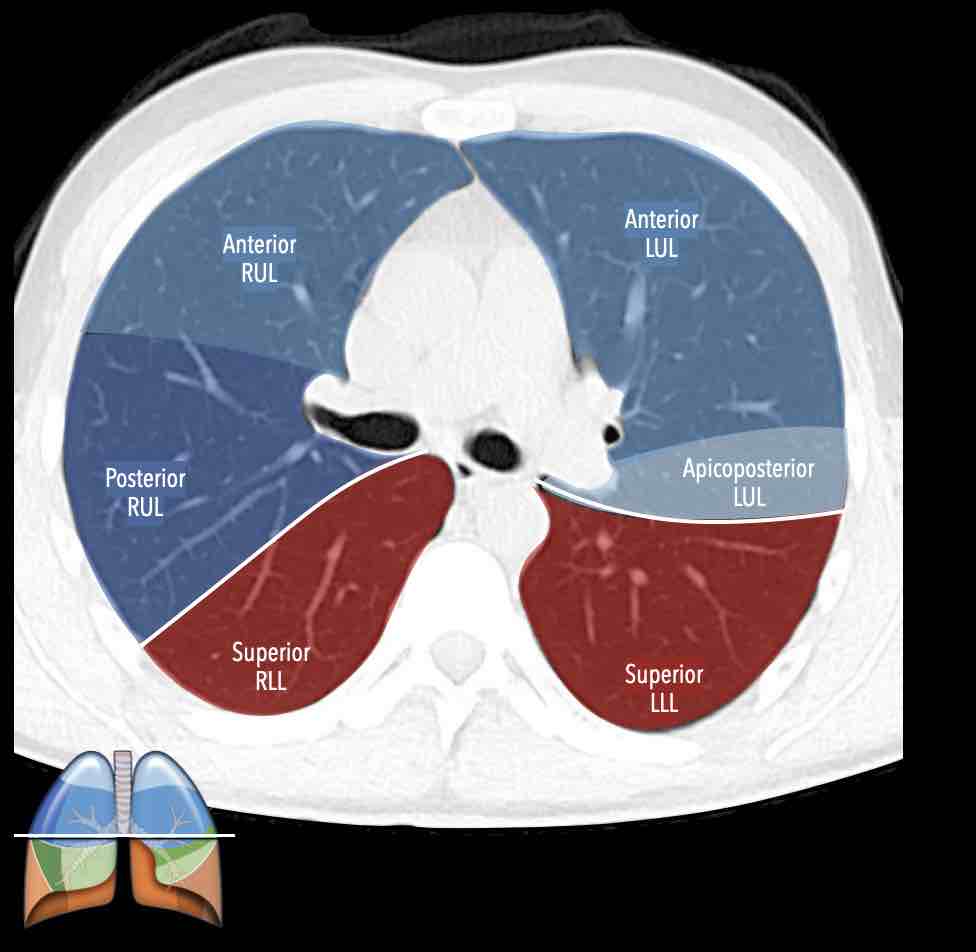

Các phân thùy phổi trên CT

Cuộn qua các hình ảnh để quan sát cách phổi được phân chia thành các phân thùy.